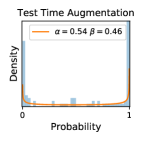

5.1 Distribution of Uncertainty Scores

Distribution of Uncertainty Scores Across Different Severity Levels As explained in Section 3, each uncertainty metric essentially defines an order/ranking among the data points. We conducted an analysis to better understand what data will be assigned high uncertainty under a particular uncertainty metric . Picking out the highest ranked data points (), we calculated the ratio of data points from each SL. Figure 4 summarizes the results as box plots for the Kaggle-DR and the Messidor-2 datasets; additional detailed statistics can be found in Table S.1 in the supplementary materials. From the plot and table, SL1 & SL2 examples account for a higher proportion among the top-ranked uncertain examples across the three ensemble methods. This finding matches our intuition that incipient disease examples (SL1 & SL2) are more likely to be considered uncertain by ensemble methods due to their ambiguity.

Comparing the three ensemble methods in Figure 4, the stacking ensemble method has the highest ratios of SL1 & SL2 data among the high-uncertainty examples it identified under both mean and var. TTA showed slightly better performance than MC-dropout but still falls behind the stacking ensemble method. Considering the fact that SL0 examples accounted for the majority of the dataset, the stacking ensemble method was much more precise (specific) in selecting truly ambiguous data points that were difficult to classify. From Figure 3, we can also see that the stacking ensemble method greatly outperformed the other two methods in finding false negatives under both mean and var uncertainty metrics.

In contrast, the MC-dropout method showed the worst overall performance among the three, as it can be seen from the high ratios of SL0 examples among the uncertain negatives in Figure 4. The histograms in Figure 2 provides another perspective to look into the phenomenon, where a decent proportion of MC-dropout model’s predictions on SL0 inputs entailed low confidence (far from 0 or 1), which from another angle explained why MC-dropout was less specific in terms of lower FNP; many no-DR inputs (i.e. SL0) were erroneously assigned high uncertainty by MC-dropout models.

It is still an open question why the evaluated MC-dropout networks signaled relatively high uncertainty on SL0 & SL3 & SL4 data that are less likely to be ambiguous. We conjecture that much of the “uncertainty” indicated by disagreement among test-time dropout samples actually reflects the stochastic nature of dropout networks rather than the real decision uncertainty associated with the data. It is worth noting that the MC-dropout model we evaluated was not weak per se; they all achieved above Area Under Curve (AUC) scores on test sets. The weakness of individual test-time samples (which explains their low-confidence predictions on SL0 & SL3 & SL4) might have been hidden when they are aggregated into an ensemble—a well-known advantage of ensemble learning. Our results suggested that the uncertainty information given by implicit ensemble methods such as MC-dropout and TTA might not be as reliable as that from explicit ensemble approaches (e.g., stacking ensembles). Similar findings on MC-dropout can be found in some previous papers [1].